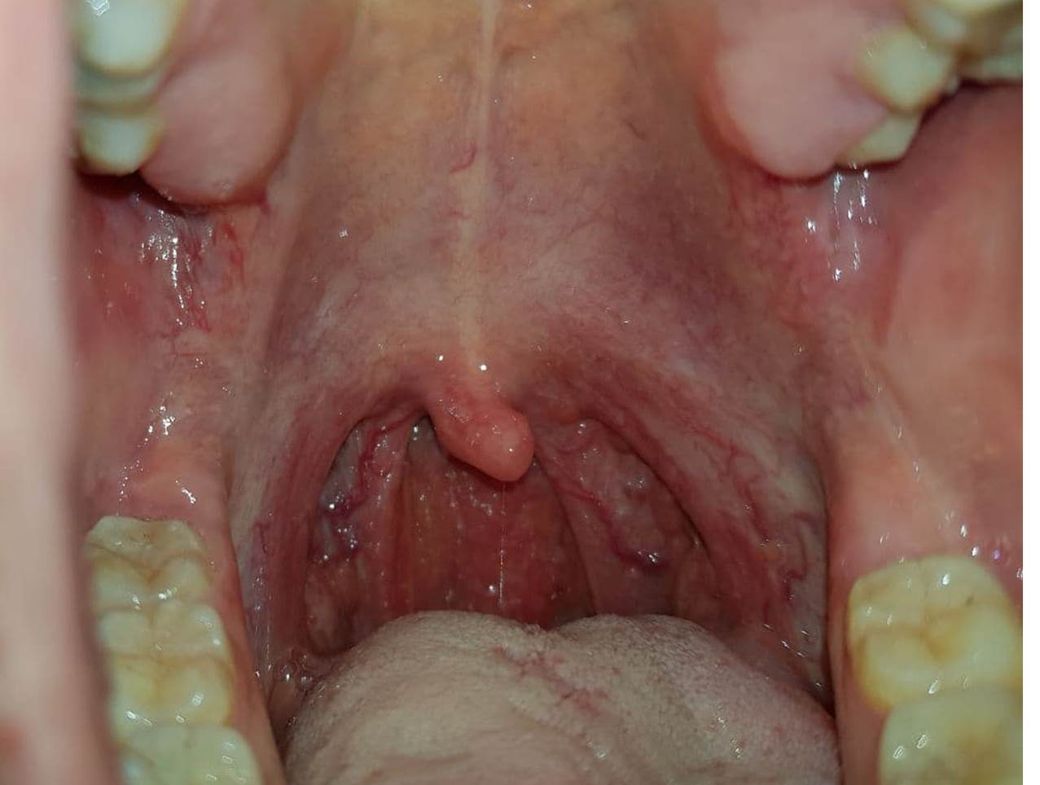

목에 염증같은게 있는거 같은데 현재 제 목구멍 상태좀 확인해주세요 .

목구멍에 보면 핏줄이 보이며, 목구멍 내부가 퉁퉁 부어있는것처럼 보입니다.

아래 사진 있는데 협오스러우니 더럽거나, 징그럽다고 느껴지실 수 있어 미리 말씀드립니다.